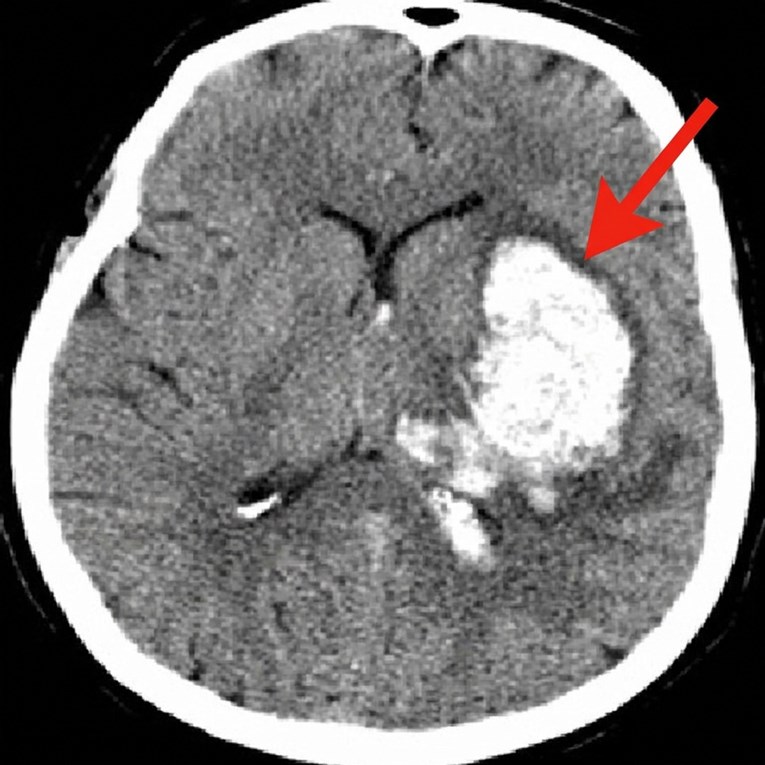

Moždani udar je među vodećim uzrocima smrti. Nađen mogući lijek